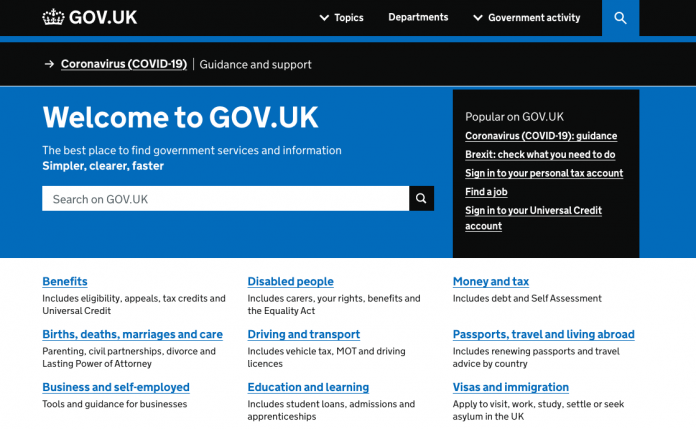

Neuromodulation clears symptoms of severe, untreatable depression

Targeted neuromodulation may be a future method to help those with severe, untreatable depression - traditionally, this is used to correct misfiring brain circuits in people with epilepsy or Parkinson's.